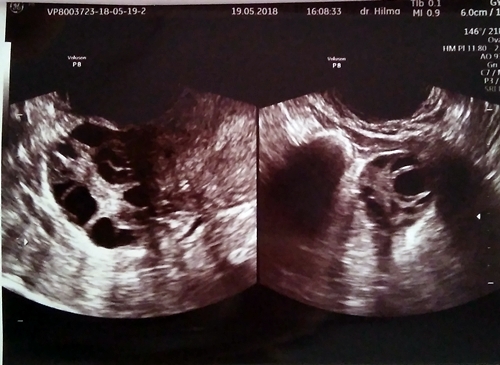

Gambar Usg Sel Telur Matang

BEGINI GAMBAR SEL TELUR YANG SUBUR… - dr Yudhistya SpOG | Facebook Story of My Journey: TTC Journey #2 USG Folikel dan Hasil Analisa Sperma Aku dan PCOS (Hasil USG Trans Vaginal) - JalanSenja.com Cerita Promil 4 - Polycystic ovary (PCO) - Fika Putri Cerita Promil 2 - USG Transvaginal dan Tes Sperma - Fika Putri Semua Akan Terjawab di Waktu yang Tepat - kumparan.com Promil Story : MIMPI BURUK ITU BERNAMA PCOs - The Arsalan Family Journal Penting Dilakukan Wanita, Ketahui Sel Telur Dalam Tubuhmu Jangan Sampai “Mandul” Karena Kehabisan Program Hamil di Dokter Lusiana Irene, SpOG Jogja Manusia sedikit tahu..sel telur kecil tidak mungkin hamil | Dr Suryo, SpOG - Kesehatan Reproduksi C e r i t a C i k i: Sel Telur Kecil-Kecil EFEK PENYUBUR Pada wanita normalnya sel… - dr Yudhistya SpOG | Facebook Ikhtiar yang ke dua – Part 2 (H6-H11) – Bread and Butter Letter Promil Step 4 – Baby Journey PCOS adalah… | Kisah Ibuknda (pakai ‘k’) :D Room | ‘Aisyah Tsurayya Inart’s Story - Yah, Saya Akhirnya Hamil - I’m 1 In 10: My PCOS Story Kisah Perjuangan Terbaru Tya Ariestya Saat Jalani Program IVF | Popmama.com story of my lyfe: pejuang keturunan Nikita Mirzani Bagikan Hasil USG Bayi Kembar, Dapatkah Gen Kembar Diturunkan? - Semua Halaman - Intisari lihat hasil USG tranvaginalku wktu bulan Januari 2013 apa itu PCO? - IbuHamil.com Cerita Promil 4 - Polycystic ovary (PCO) - Fika Putri aq PCO bund, ada yg bisa bantu baca hasil USG intravagina q??? - IbuHamil.com Hasil USG Sel Telur Yang Subur - YouTube Pengalaman Bayi Tabung/ IVF (Part II) Update with Pict! | honeymenulis’s Blog Inart’s Story - Yah, Saya Akhirnya Hamil - Story of My Journey: June 2017 Ingin Terhindar dari Kista? Jauhi 4 Jenis Makanan Enak Ini Sekarang! - Semua Halaman - Grid Health Program Hamil Bulan ke-1 : PCOS Survivor | Lanalouie Embrio 3 cm berapa minggu. minggu: bayi Anda sebesar tongkol jagung BEGINI GAMBAR RAHIM YANG SUBUR… - dr Yudhistya SpOG | Facebook PCOS | medicalstudentnotes USG Transvaginal: Penjelasan, Prosedur & Manfaat (Lengkap) | Friso BILIK SONOGRAFER : Kista Ovarium Kontrol H+10 (Cek Perkembangan Sel Telur) Istilah kehamilan dipertimbangkan dengan USG. Kehamilan kebidanan dan embrio Selamat Pagi Senin Ayah Bunda. Semoga… - Dokterkandungan. id | Facebook My First USG | Story of Us Menuju Hamil – Part 2 of 3 – Edward Suhadi Apa itu PCOS? Kenapa Sulit Hamil? | Sunshine of My Life Setiap Ibu Hamil Harus Tahu, Kapan Harus Melakukan USG lewat Vagina? - Semua Halaman - Nakita Program Hamil di Dokter Lusiana Irene, SpOG Jogja Saat Sel Telur Berukuran Kecil dan Sulit Dibuahi - Health Liputan6.com Kabar Gembira, Ini Tanda Awal Sel Telur Berhasil Dibuahi oleh Sperma | Popmama.com 101+ Gambar Cek Sel Telur Paling Hist - Gambar Pixabay Kontrol H+12 (Mendebarkan, apakah sel telurnya tetap berkembang?) Program Kehamilan Balasan dari Saya Penderita PCOS, Saya Berhasil Hamil | KASKUS Pembekuan Sel Telur: Fungsi, Prosedur, dan Komplikasi INGIN HAMIL – Siklus Ovarium dan Tanda-Gejala Wanita Subur | JuliantoWitjaksono.com 6 Fakta Mengejutkan Tentang Sel Telur Wanita - YouTube Pengalaman Hamil Kembar - The Urban Mama Maimuns — PCOS? Deal with it! Berapa Sisa Sel Telur di Tubuh? Bisa Dicari Tahu | Parenting.Dream.co.id PCOS Polycystic Ovary Syndrom Apakah… - Komunitas Impian Bunda | Facebook Persiapan Hamil (4) – jurnal Ammi Wanita Hasilkan 2 Sel Telur dalam Masa Ovulasi, Bisakah Terjadi? Promil Story : MIMPI BURUK ITU BERNAMA PCOs - The Arsalan Family Journal My journey to motherhood: HSG, Tes Sperma, hingga PCO Polikistik Ovarium (PCOS): Haid sering tidak datang, Berkumis, Berjerawat, Ingin hamil sulit | Dr Suryo, SpOG - Kesehatan Reproduksi PCOS dan Metformin. Sohib karib! – Cerita Bumi Blighted Ovum | ~cahaya kebaikan~ Cerita Pengalaman Kehamilan Pertama dan Persiapan Melahirkan Anak Pertama - For The Love of Foods and Beauty Masih banyak yg belum tau.. INSEMINASI… - Bayi Tabung PMC Pekanbaru Cerita Program Hamil dengan Dokter Enny Sp.OG di Yogyakarta ~ Land of Jenganten Semua Akan Terjawab di Waktu yang Tepat - kumparan.com Fika Putri Berbagi Tips: Cara Mengetahui Masa Subur Wanita Berdasar Penghitungan serta Ciri-Cirinya - Garda Remaja GAGAL OVULASI?? SERING TERJADI PADA… - Konsultasi Promil Cepat Hamil dan Alami | Facebook Yosevina Issabela prosespersalinan Instagram posts (photos and videos) - Picuki.com Apa sebetulnya bayi tabung dan bagaimana proses menjalaninya? – Bayi Tabung Penang Di minggu kebidanan mana embrio terlihat. Minggu berapa embrio terlihat pada USG? Apakah prosedurnya aman pada tahap pembentukan anak PCOS itu Variable dan Sangat Rumit Prosedur Bayi Tabung: Sebelum dan Sesudah Mengikutinya - Smarter Health Mengenal Kehamilan Kosong atau Blighted Ovum (BO) - Kompasiana.com Cerita Promil, Perjalanan menuju kehamilan (long story short, I finally got pregnant) - Nyonyah Intan Sindrom Ovarium Polikistik (PCOS) 4D Gallery | Dr Suryo, SpOG - Kesehatan Reproduksi Kapan USG direncanakan selama kehamilan. Apakah saya perlu mempersiapkan prosedur? Keadaan organ reproduksi wanita Irish Bella Hamil Anak Kembar, Sang Ibunda Tak Sangka Bakal Punya 2 Cucu - Halaman all - Tribun Batam Lapsus Kista Ovarii - Apriamalia - [PDF Document] Success story – GLADIOOL IVF RS Indosehat Solo, Jl Solo Sragen Km 11, Kebakramat, Karangdawa (2020) Saya Penderita PCOS, Saya Berhasil Hamil | KASKUS September 2014 - Pipit Widya Aku dan PCOS (Hasil USG Trans Vaginal) - JalanSenja.com Pengalaman PCOS-ku yang Berhasil Hamil Alami - kumparan.com Apakah USG mempengaruhi kehamilan. Bagaimana ultrasound mempengaruhi embrio? Ultrasonografi dilakukan hanya atas kesaksian dokter atau mungkin atas permintaan ibu BAB III - [DOCX Document] Kista Ovarium. - ppt download Biaya USG 3 & 4 Dimensi di Karawang - Perawatan Kesehatan Cerita Pengalaman Kehamilan Pertama dan Persiapan Melahirkan Anak Pertama - For The Love of Foods and Beauty Wanita Punya 400 Sel Telur Setiap Menstruasi, Kenapa Susah Hamil? - Semua Halaman - Nakita Tragis Si Ibu Hamil Dibunuh, Bayi di Dalam Kandungan Dicuri - Halaman all - Warta Kota Perlukah USG Transvaginal saat Program Hamil? | Popmama.com 13 Tanda - tanda Kehamilan Awal yang Bisa Dipercayai - Mamapapa.id Melahirkan bayi kembar pada minggu-minggu kehamilan. Dapatkah dokter tidak melihat bayi kembar dengan USG: diagnosis dini kehamilan ganda PROSES DAN BIAYA INSEMINASI 1. USG USG… - dr Yudhistya SpOG | Facebook